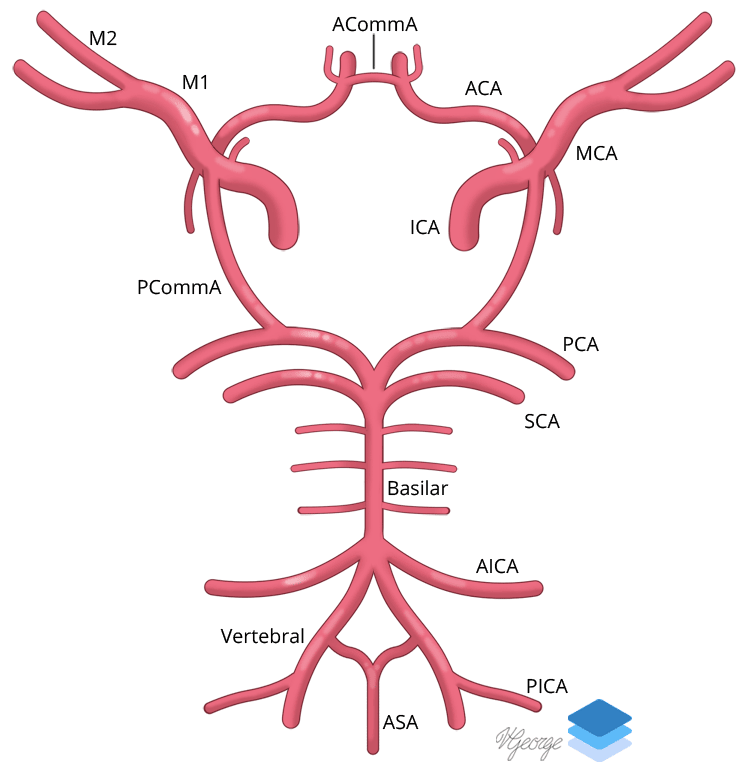

Circle of Willis